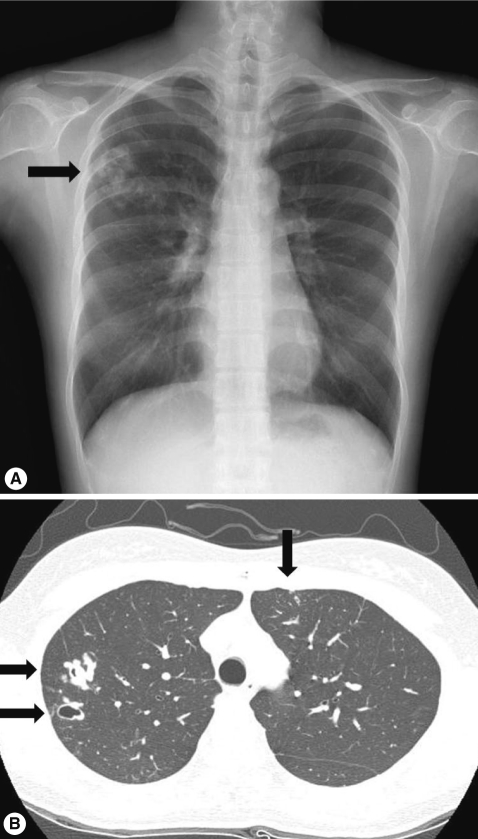

3. A follow-up chest X-ray at 4 months after the treatment showed interval decrease in the size of multiple nodules in the right lung and CT at 6 months after the treatment revealed markedly diminished nodules in size with cystic changes (

Fig. 3).

Fig. 3Follow-up chest X-ray and CT. (A) Interval decreases in the size of multiple nodules are shown in the right lung on the chest X-ray 4 months after treatment (arrow). (B) Markedly diminished nodules in size with cystic changes are observed in both lungs on CT 6 months after treatment (arrows).